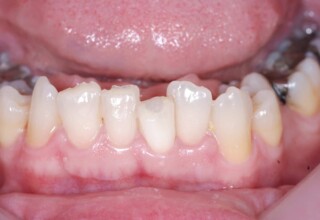

Restoration of bilateral diastemas between central and lateral incisors.

Diastemas were created mainly because of narrow laterals. After orthodontic treatment was finalized, the diastemas were closed with two composite resin restorations.